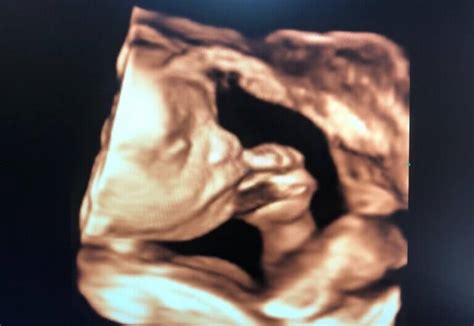

După 11 săptămâni de gestație, fătul este suficient de dezvoltat pentru a permite o analiză detaliată a anatomiei sale. Această etapă este crucială pentru depistarea precoce a modificărilor specifice asociate anomaliilor cromozomiale. În timp ce unele organe, precum inima, sunt complet formate structural și funcțional, altele, precum plămânii și sistemul nervos central (inclusiv creierul), continuă să se dezvolte semnificativ pe parcursul sarcinii.

În această perioadă, fătul capătă aspectul unei ființe umane, deși craniul poate fi proporțional mai mare decât la adult. Mișcările corpului și ale membrelor devin vizibile, oferind o imagine completă a dezvoltării fetale.

Metode de Efectuare a Ecografiei de Morfologie Fetală

După 11 săptămâni și 0 zile de gestație, ecografia de morfologie fetală se poate realiza, în majoritatea cazurilor, pe cale abdominală. Totuși, anumite condiții, precum poziția fetală, mișcările fetale, grosimea peretelui abdominal matern (stratul adipos sau cicatrici ecogene) sau poziția uterului (uter retroversat), pot împiedica vizualizarea corectă. În aceste situații, se poate recurge la examinarea pe cale transvaginală, care oferă o rezoluție a imaginii net superioară, deși cu o mobilitate redusă a sondei.